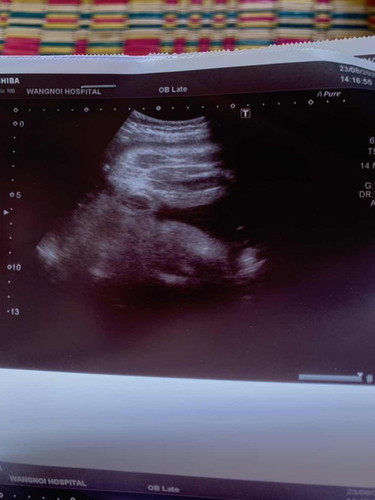

แม่ๆช่วยดูหน่อยคะว่าน้องเป็นเพศอะไร

ลูกสาวค่ะ ถ้าเป็นผู้ชายจะมีอวัยวะเพศยืนออกมาที่มองออกว่าเป็นผู้ชายค่ะ

3กลีบลูกสาวค่ะ บ้านนี้ก็ลูกสาว😊

ลูกสาวล้าน%จ้า

ผู้หญิงค่ะ

ลูกสาวจ้าแม่

เพศหญิงค่ะ

ของเราลูกสาวก็แบบนี้ค่ะ เป็นกลีบๆมีขีดตรงกลางค่ะ